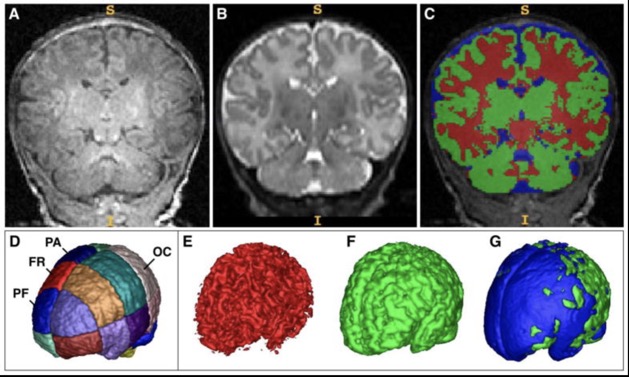

1. volume total de matière grise (GM) plus faible en particulier dans les régions cérébrales préfrontales et frontales.

2. volume total de liquide céphalo-rachidien (LCR) plus élevé en particulier dans les régions préfrontales, frontales et pariétales, mais pas occipitales

=> altération des fonctions exécutives et le contrôle inhibiteur.